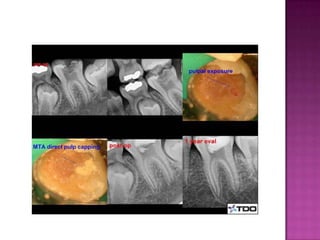

The document discusses pulp therapy for primary and permanent teeth. Pulp therapy is divided into vital pulp therapy and non-vital pulp therapy. Vital pulp therapy is used for primary teeth with normal pulps or reversible pulpitis, and involves procedures like pulpotomy to maintain the vitality of the remaining pulp. Non-vital pulp therapy is used for primary teeth with irreversible pulpitis or necrotic pulps, and involves procedures like pulpectomy to remove the entire pulp. Maintaining primary teeth has benefits such as preventing malocclusion, aiding mastication, and preserving space for permanent teeth.